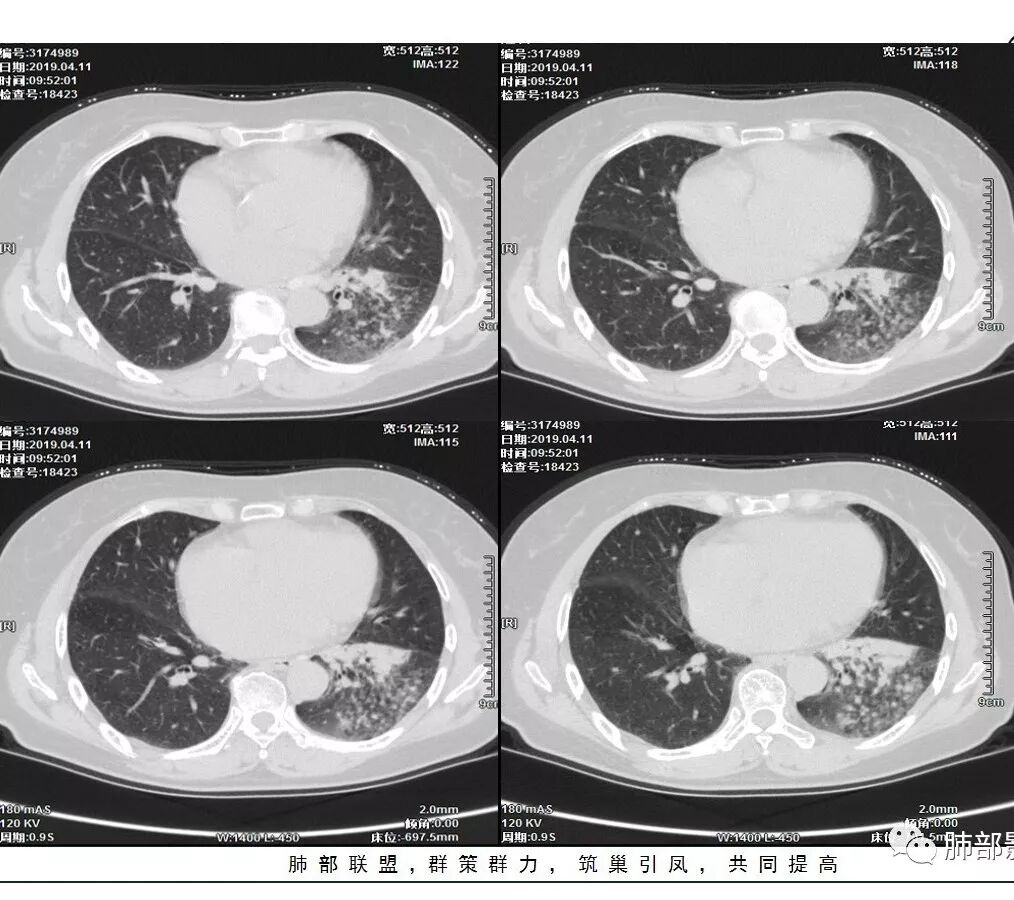

胸CT:左下叶实变影及磨玻璃影,小叶间隔增厚,内部支气管扩张、僵直。左肺门淋巴结肿大、钙化。考虑肺腺癌?合并感染

胸CT:左下叶基底段支气管狭窄,沿支气管分布斑片实变影、网格影、磨玻璃影,支气管充气征,无重力效应,左肺门淋巴结肿大、钙化。

1、主病灶  左下叶斑片状、大片状致密影

2、两肺马赛克灌注

3、两侧肺门区钙化淋巴结

2.左肺下叶片状影及多数有边界的结节影,较散,多形性,密度不均(注意许多老师提到这个特点还是比较明显的)。左肺下叶体积未见缩小。

3.病灶强化比较明显。

4.左下叶支气管壁增厚,管腔不均匀狭窄,没有堵塞

5.肺门纵隔见增大钙化淋巴结。提示曾经存在慢性病损可能。